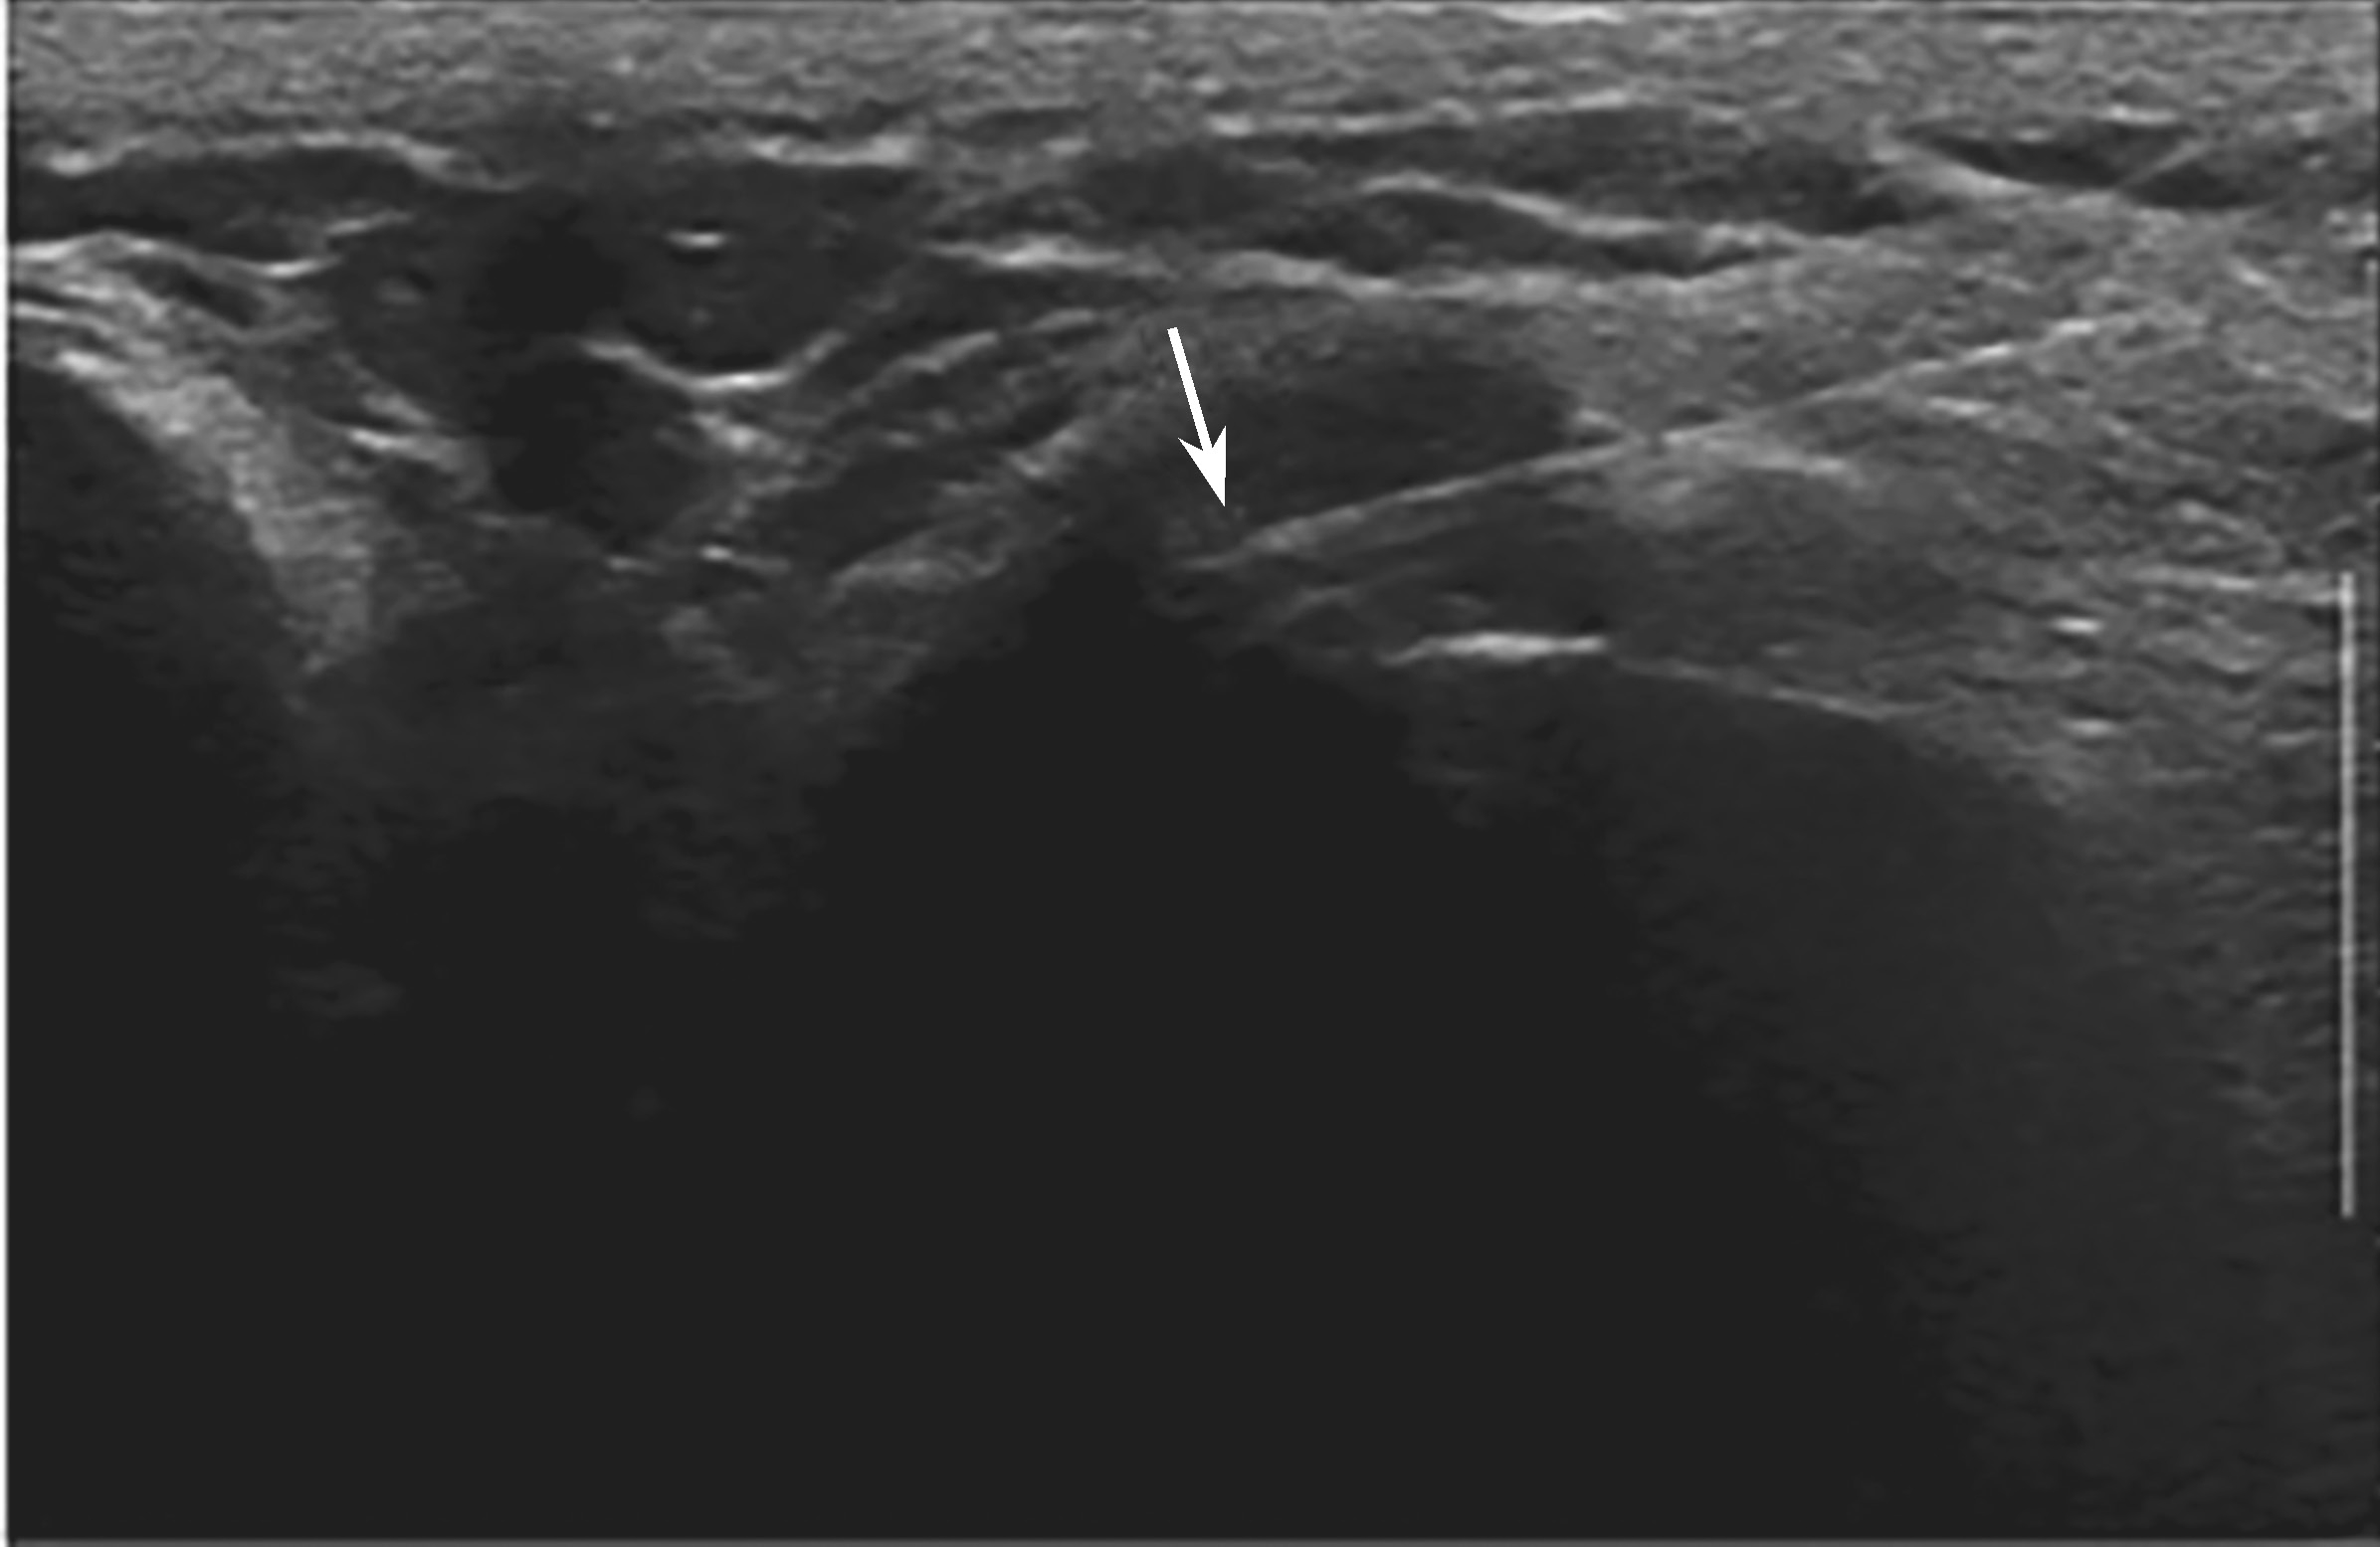

▲ 图2-5-2 超声引导下胸锁关节腔介入治疗超声图

平面内进针法;箭头:穿刺针进入胸锁关节

平面内进针法,引导针尖进入胸锁关节腔(图2-5-2)。

避免穿刺针穿透胸锁关节腔刺伤其后方重要结构。与肩锁关节一样,胸锁关节腔较小,药物用量不宜过多,防止溢出。